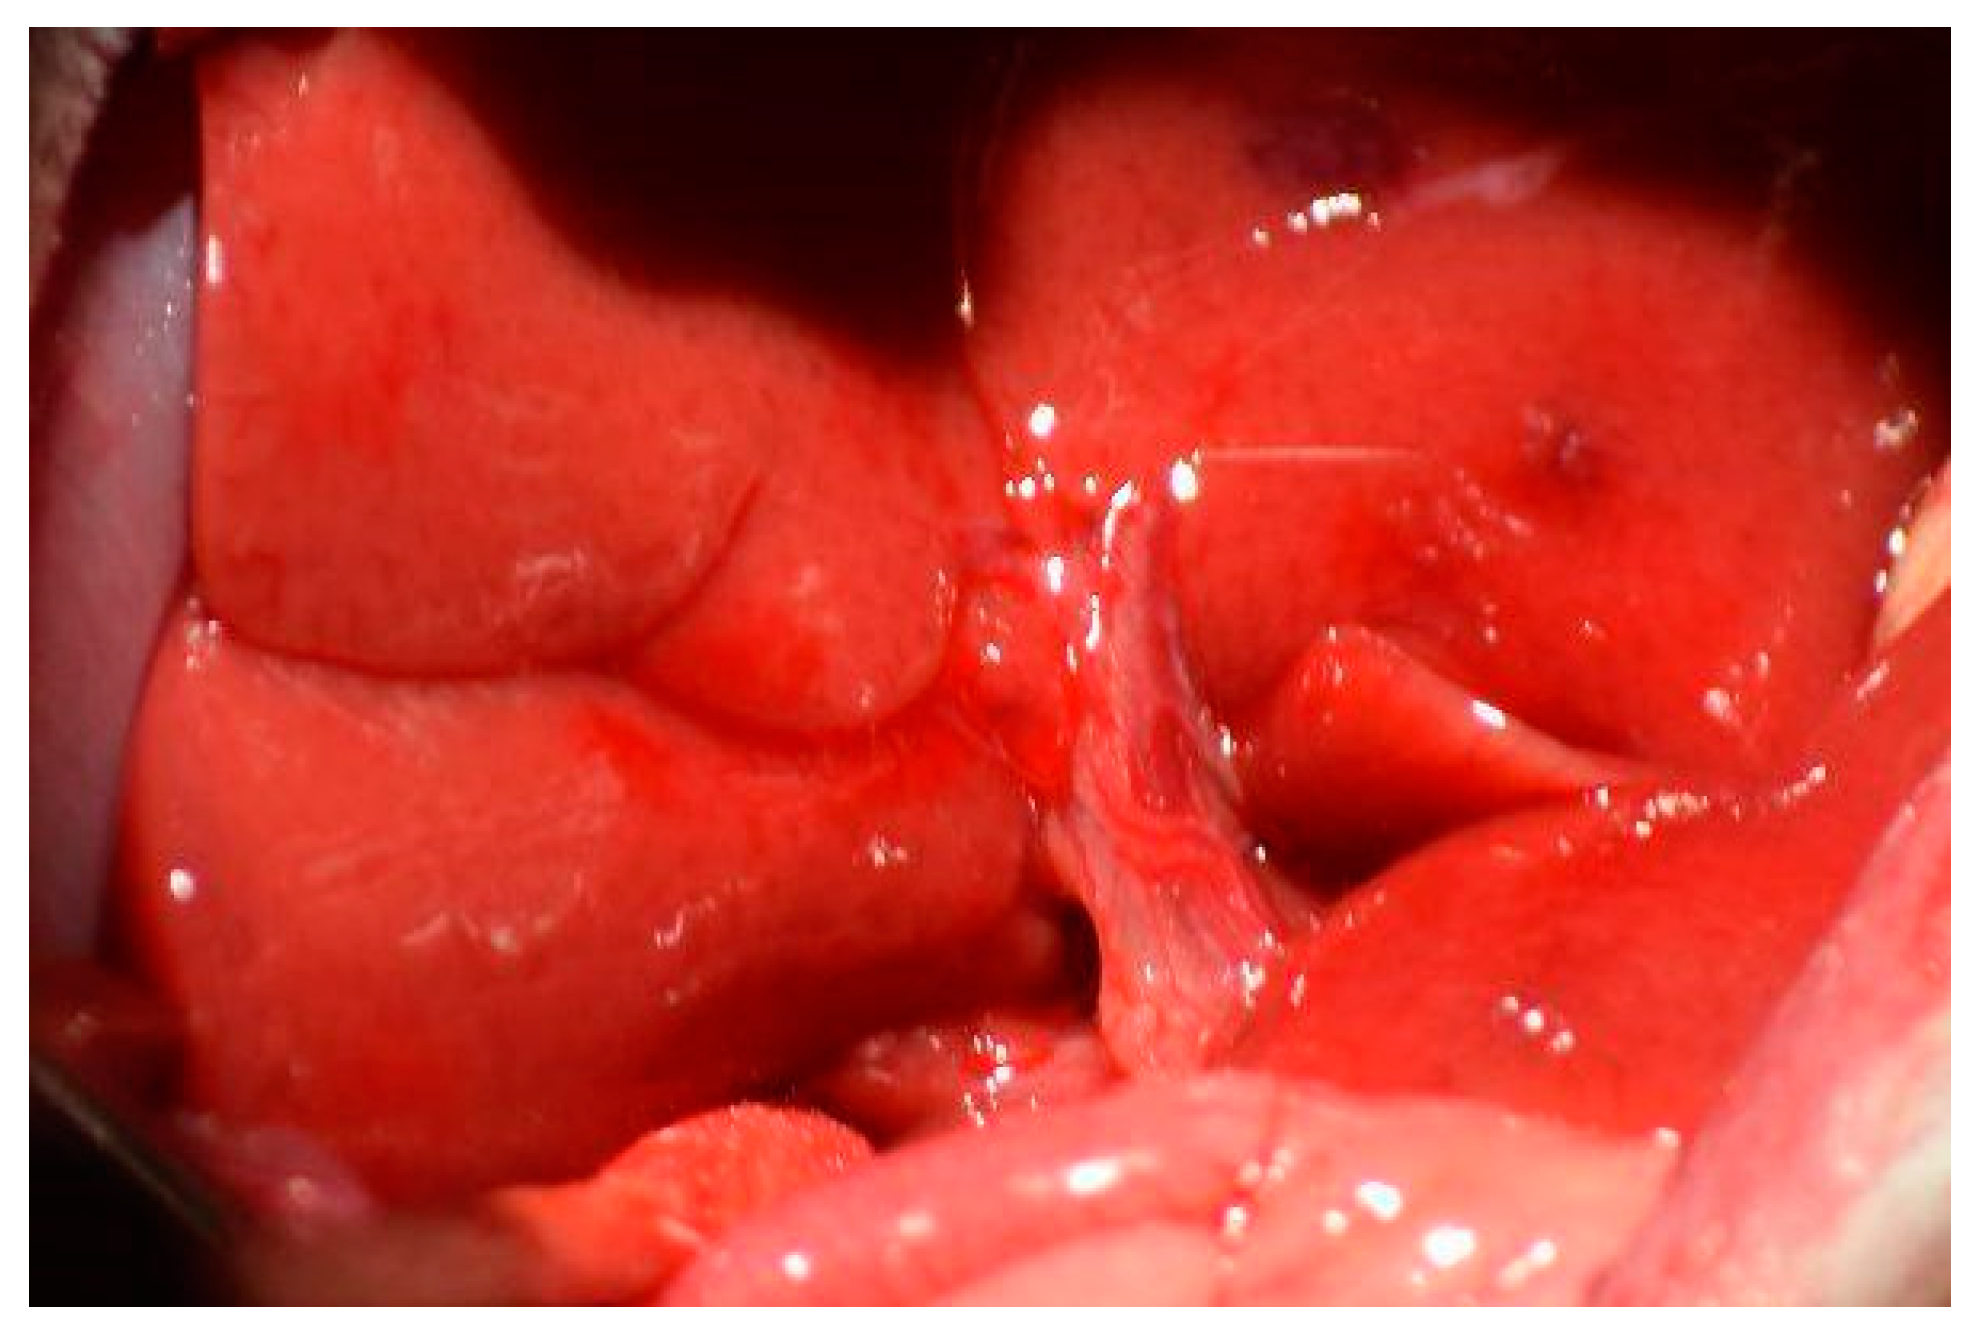

The medial and left lateral lobes are lifted to expose the hilum (Figure 4). Using a Leica Wilde M651 surgical microscope (Leica Microsystems, Bensheim, Germany) at 20 × power magnification, visual access is focused on the portion of the hilum that supplies the median and left lateral lobes. The membrane between the bile duct and hepatic artery is punctured using a curved jaw micro needle holder, and 4-0 silk thread is pulled through the separation. The membrane between the portal vein and inferior vena cava is then punctured using a curved jaw micro needle holder, and one end of the 4-0 silk thread is pulled through the separation. As a result, the thread holds the hepatic artery and portal vein that supplies the median and left lateral lobes. The hepatic artery and portal vein are ligated, which stops all inflow to those lobes. Visual confirmation of successful ligation can be obtained through a color change in the lobes from bright pink to brown. Figure 5 depicts each stop of this hilum dissection and ligation.

Figure 4. Exposed hilum of the animal. Visual access was acquired by lifting the median and left lateral lobes against the visceral peritoneum.